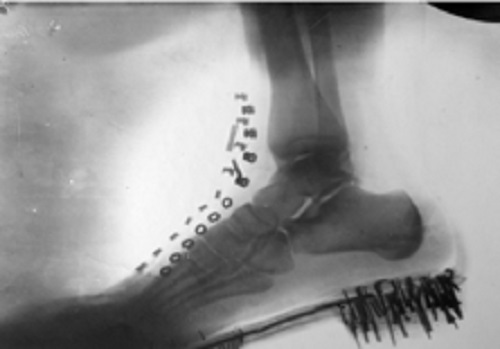

Izložba će predstaviti istorijski razvoj i primenu rendgenske tehnologije u medicini, od otkrića rendgenskih zraka do danas, sa posebnim naglaskom na doprinosima koji su u oblasti rendgenologije ostvarili Nikola Tesla i Mihajlo Pupin. Ciljevi izložbe su i predstavljanje uspeha domaćih preduzeća u razvoju proizvodnje rendgenskih aparata i opreme.

Pored fotografija i dokumenata, na izložbi će moći da se vide i stari rendgenski aparati, oprema i sredstva za ličnu zaštitu od zračenja, prve rendgenske cevi proizvedene u Jugoslaviji, ali i najnoviji digitalni rendgenski uređaji. Sastavni deo izložbe su sadržaji u obliku virtuelne stvarnosti (VR) i edukativne digitalne igre za decu i omladinu koje su kreirali najbolji polaznici besplatnih edukativnih programa za razvoj igara, prijatelja izložbe Nordeus Haba i Krater trening centra. Tokom trajanja izložbe biće organizovana stručna vođenja, predavanja i edukativne radionice za decu, omladinu i studente.